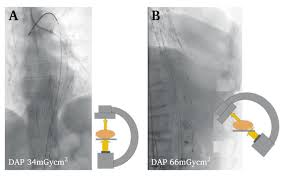

European Journal of Vascular and Endovascular Surgery